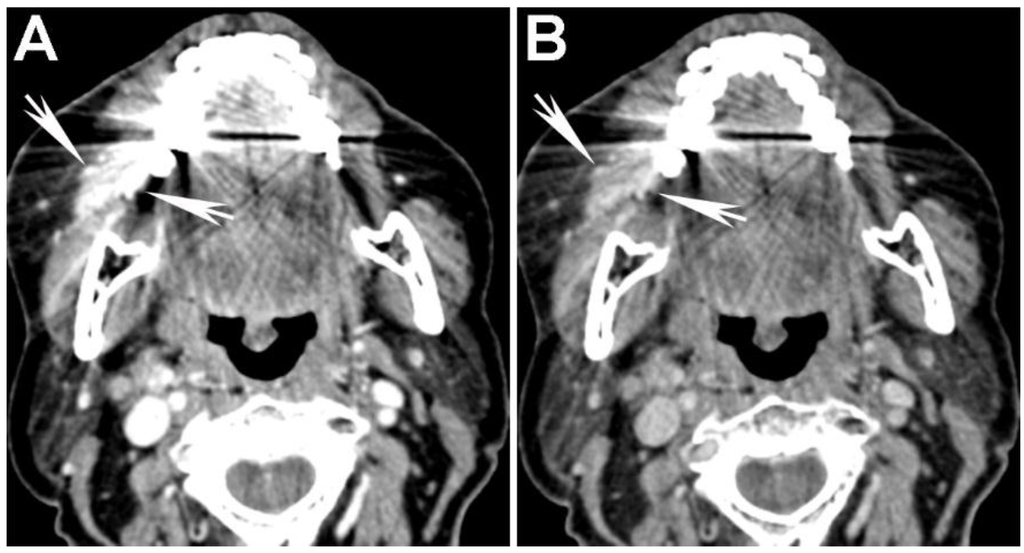

Figure 6. Use of high energy DECT virtual monochromatic images (VMIs) for dental artifact reduction. (A) 65 keV and (B) 140 keV VMIs are shown from the same level in the neck. Note significant reduction of artifact such as in the region of retromolar trigone (black arrow) or oral tongue (white arrow) on the higher energy, 140 keV VMI compared to the 65 keV VMI.